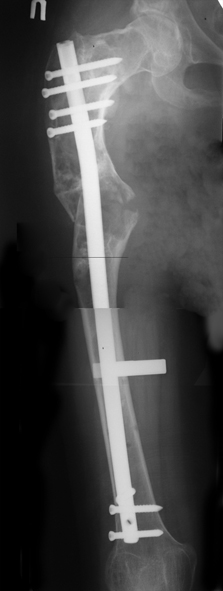

Шахсувар Асадов 18 Ноябрь 2009, 16:04

Беспокою вас на счет деформации правой бедренной кости после патологических переломов.

Мне 15 лет. Случилось все когда мне было 10 лет 26.12.04 я был дзю-доистом и в одном из соревнований сломалась правая бедренная кость. перелом был внутренний со смещением. Взяли и сделали операцию, поставили пластинку и тем самым заложили инфекцию. Потом кость начала гнить и сняв пластинку, через три месяца поставили аппарат Илизарова. Он отлежал месяцев шесть с мая по сентябрь. и когда снимали кость снова отошла. то есть сломалась. по правую сторону бедра были дырки из которых шел гной и которые закрылись уже в 2006 году. далее поправив поставили в гипс который остался больше шести месяцев. прошли месяцы и все вроде было в порядке. потом опять сломалась изза простейшей причины в августе 2006 года. опять поставили в гипс. прошло время и снова когда спускался с бордюра сломалась в четвертый на данный момент последний раз 23 мая 2008 года. с тех пор кроме патологических разломов кости тревожила еще одна проблема. та самая деформация. только со временем она становиться еще сильней.

Прошу вас помочь в ситуации. живу в Баку, Азербайджане. Здешние врачи говорят что можно исправить ТОЛЬКО Илизаровским аппаратом. что меня сильно беспокоит так как он уже у меня был.